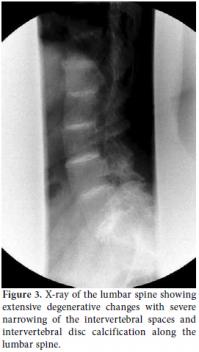

Radiographs of the lumbar spine showed extensive degenerative changes with severe narrowing of the joint spaces together with intervertebral disc calcification along the lumbar spine, fusion of vertebral bodies in the upper lumbar spine, osteophyte and bone bridge formation, and loss of lumbar lordosis (Figure 3). Additionally, an X-ray of the knee joints determined that there were degenerative changes with joint space narrowing, and X-rays of both shoulders showed decreased joint spaces with degenerative changes in the articular portion of the humeral head. The patient also complained of difficulty walking and of an inability to move. Eventually, she became disabled. The patient used to have high-protein content meals but had changed her diet to one of low protein since being diagnosed with AKU. She was also prescribed 1 g of vitamin C daily. She has 13 children (two sons and eleven daughters), and there is a family history of AKU, with two sons and six daughters having also been diagnosed with the same disease.

Spinal changes that occur with AKU include severe disc calcification, disc space narrowing, and sclerosis, primarily in the dorsolumbar spine rather than the lumbosacral spine.[16] The calcification of intervertebral discs is pronounced at the periphery and tends to spare the central nucleus pulposus, with its wafer-like pattern.[17] Large peripheral joint involvement usually takes place years after ochronotic spinal involvement, and the small joints of the hands and feet, wrists, elbows and ankles are rarely affected. The knees are the most frequent target, and knee joint effusion may also occasionally occur. After the knees, the hips are affected the most, and rapid deterioration is often seen in these joints with AKU.[18]